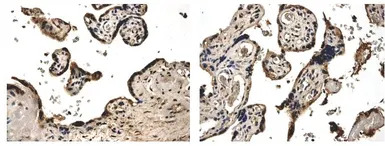

IHC-P analysis of formalin fixed human placenta tissue using GTX52467 PDGF beta antibody [5F66].